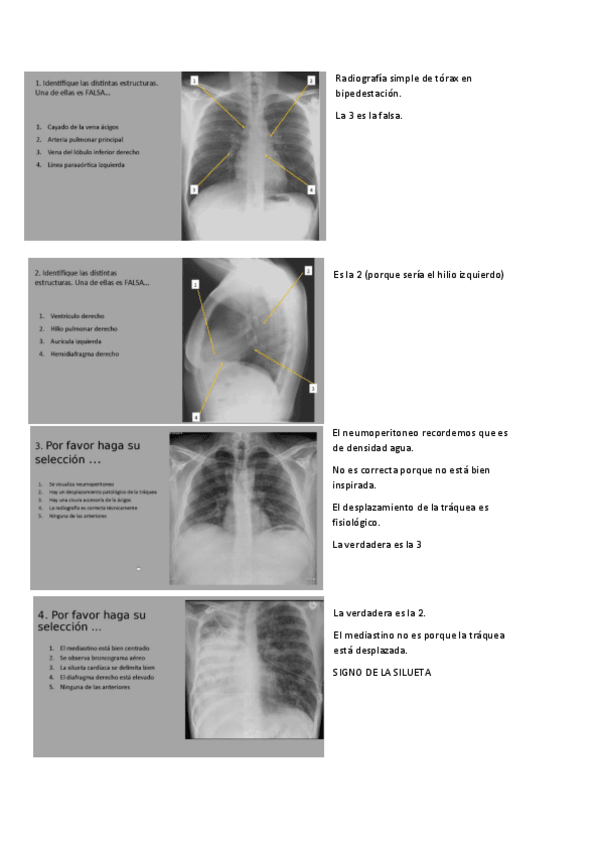

SEMINARIOS-RADIOLOGIA-TORAX.pdf

Apuntes - SEMINARIOS-RADIOLOGIA-TORAX.pdf